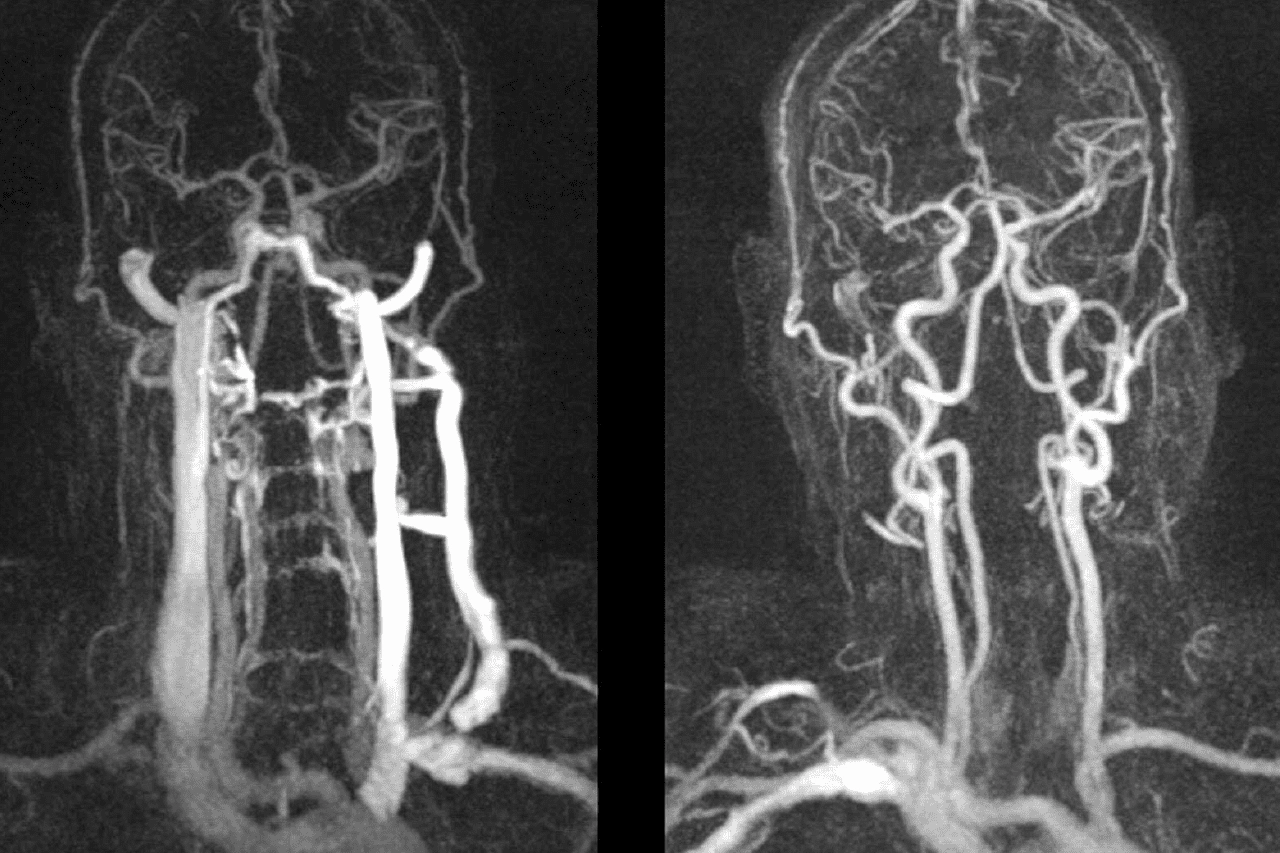

Вот это самое главное. Существует популярное заблуждение, что МРТ точнее УЗИ. Ведь очень часто после проведения ультразвуковой диагностики направляют пациента для проведения МРТ. Однако при изучении извилистости сосудов данный метод исследования несёт мало информации. Даже в сосудистом режиме МРТ просто покажет место локализации зажима. Это как смотреть на снимок реки и не понимать с какой скоростью она течёт. А для лечения хронических заболеваний, связанных с нарушением кровотока в шейном отделе позвоночника, знать скорость — важнейший этап диагностики.

Изображение сдавленных позвоночных артерий

Изображение снимака МРТ позвоночных артерий: пример